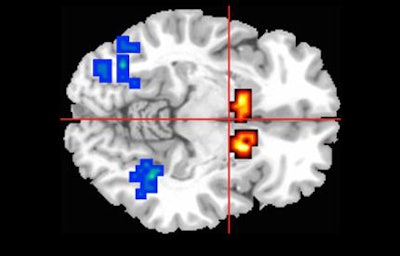

All participants underwent MRI scans while performing a memory task to engage three regions of the brain involved in psychosis.

Among those at risk for psychosis, the subjects who were given cannabidiol showed less-severe abnormal brain activity than those who received a placebo, suggesting that cannabidiol can help readjust brain activity to normal levels.